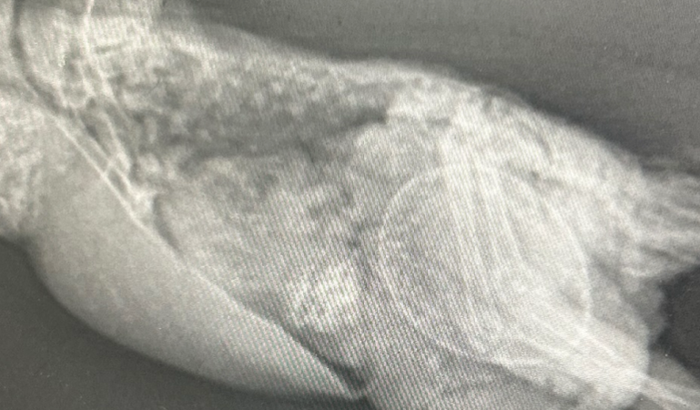

Meu nome é Thamyres e criei essa vaquinha para poder ajudar nos custos da cirurgia da minha calopsita ela está com um ovo estourado dentro do abdômen e um ovo preso ainda

Os valores são pra ajudar na internação e cirurgia agradeço de coração quem puder me ajudar